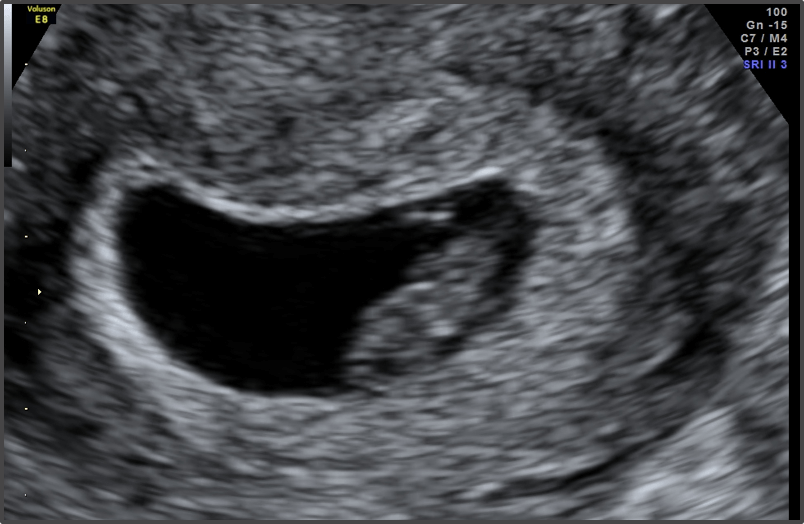

Pregnancy Calculator - Week 7

Baby is the size of Blueberry

Approx Baby Weight: 1.3g

Approx Baby Size: 1.2 cm